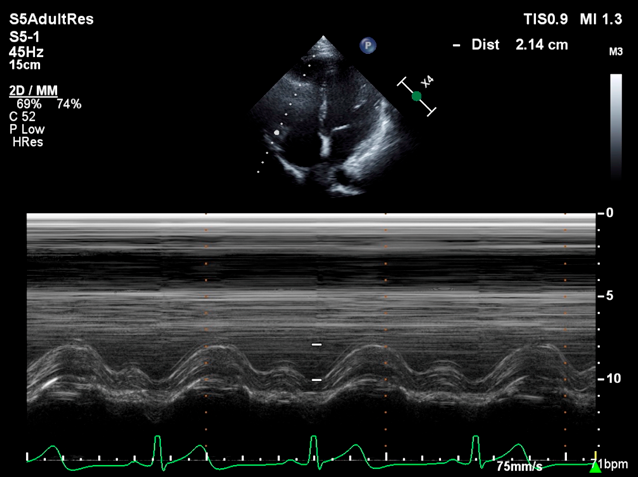

非侵襲的な右室肺動脈カップリングの評価方法としてTAPSE/SPAP比があり,心エコーで評価することができるため簡易的な指標である.TAPSE(tricuspid annular plane systolic excursion)とは三尖弁輪収縮期移動距離であり,右心室の長軸方向の収縮能を評価する方法で,心尖部四腔断面からM-mode法で測定が可能である(Fig. 4).右室収縮機能障害を示唆するCut-off値は,15 mmから17 mmまで様々な報告がある8–10).弁輪のみの動きであるため角度依存性であり右室全体の機能を反映できない点や,前負荷に影響されやすい点など限界がある指標である.しかし簡便な計測方法であり,再現性のよいことから臨床的には有用な指標といえる.後負荷の指標である収縮期肺動脈圧(SPAP: systolic pulmonary artery pressure)の推定には,前述したように三尖弁逆流最大血流速度から簡易ベルヌーイ式から算出され,右房圧加える右室収縮期圧を求める.右房圧は下大静脈の呼吸性変動を用いて推定されるが,実際には一律5 mmHgまたは10 mmHgとして算出されていることも多い11)

Pediatric Cardiology and Cardiac Surgery 39(4): 209-216 (2023)

Fig. 4 Determination of the tricuspid annular plane systolic excursion in preserved right ventricle function with severe pulmonary arterial hypertension using M-mode in apical four-chamber view